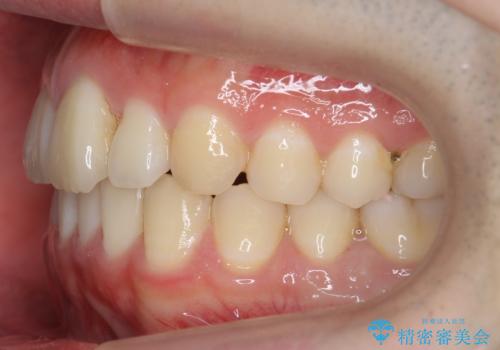

- 前歯のがたつきを主訴に来院。

左下の奥歯を後ろに移動して、中に入ってすれちがっていた小臼歯を並べました。

巷(ちまた)で大きく宣伝している某 格安マウスピース矯正では、奥歯を後ろに動かすことはできないです。

他院で歯を抜かずにマウスピースで難しいといわれた方、ぜひご相談ください。

奥歯を後ろに移動させるために、矯正用のミニスクリューを用いました。(インプラント矯正)